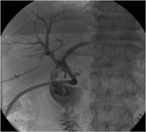

Pancreas graft salvage after successful endovascular treatment of Y graft pseudoaneurysm

V A L Huurman and J H P Lardenoye

Journal of Surgical Case Reports, Volume 2019, Issue 5, May 2019, rjz124, https://doi.org/10.1093/jscr/rjz124